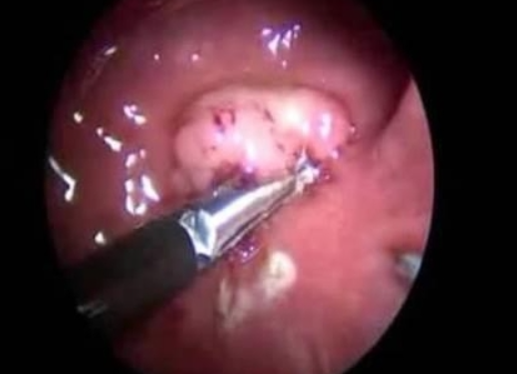

1) 수술적 치료

직장암 치료의 핵심은 수술입니다. 암 조직 주변을 포함하여 암이 퍼질 가능성이 있는 림프절까지 함께 제거해야 합니다. 최근에는 복강경을 이용한 최소 침습 수술도 널리 시행되고 있습니다.